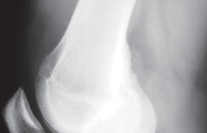

التصوير الطبي ضروري لتأكيد التشخيص وتحديد مدى تلف المفصل:

-

الأشعة السينية العادية (Plain Radiographs):

- المنظر الجانبي (Lateral): يُظهر الركبة من الجانب.

- المنظر الخلفي الأمامي المثني (PA Flexed): يسمح بتقييم أفضل للجزء الخلفي من الركبة وقد يكشف عن تغيرات أكبر في الحجرة الخلفية الوحشية.